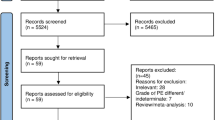

Several important contributions in the PE management have been recently published. New scoring systems, such as the PERC rule and YEARS, are used to effectively rule out PE; and stratification scores such as Bova and Hestia were validated. New evidence was favorable to support the use of direct oral anticoagulants in morbidly obese and end-stage renal disease patients; although, not in patients with antiphospholipid antibody syndrome. New studies of catheter-based thrombectomy for acute PE were also published. However, a new statement from the American Heart Association criticizes the lack of randomized trials to support the use of catheter-based interventions in acute PE. Contributions about the cardiopulmonary support in massive PE patients, including ventilation techniques, vasopressors, inhaled pulmonary vasodilators and extracorporeal membrane oxygenation are available. Finally, the advantages and disadvantages of the impact of Pulmonary Embolism Response Teams in the care of acute PE patients.